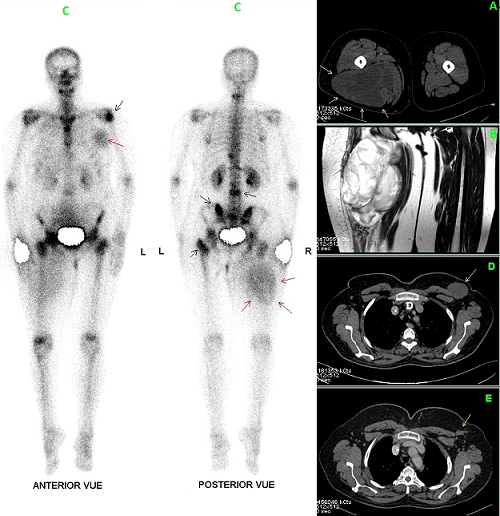

Soft tissue uptake of 99mTc-MDP in a case of myxoid liposarcoma with breast metastasis

Breast metastasis arising from non mammary malignancy is very rare and occurs in malignant melanomas, sarcomas, lung cancers, ovarian tumors, renal and thyroid carcinomas. Few cases of breast metastasis from myxoid liposarcoma have been reported in the worldwide literature. We report herein a case of a 51-year-old woman with 2-year history of a slowly growing, painless mass of the right proximal thigh. Imaging investigations showed an intermuscular mass with low-attenuation areas on the CT scan (A) and high signal intensity on T2-weighted MR images (B). Material obtained by biopsy revealed a myxoid liposarcoma. A bone scan performed as part of the initial staging process showed multiple hot spots suggestive of skeletal metastasis in addition to increased soft tissue tracer uptake projected over the right proximal thigh and the left mammary gland corresponding respectively to the primitive tumour and a breast metastasis (C). Chest CT scan showed a left breast mass with similar attenuation feature to the primitive tumour (D). The patient was treated by six chemotherapy cycles (Doxorubicine, Ifosfamide) with good control of his disease at tree years follow up (E). Myxoid Liposarcoma is a rare soft-tissue tumour with a possible aggressive evolution leading to intensive chemotherapy protocols. Soft tissue uptake on bone scan is exceptional, but can occur in a large spectrum of disease. In this case, necrosis and high-water content of myxoid tissue, reflected as marked high signal intensity on T2-weighted MR images, may contribute to the soft tissue uptake mechanism of the bone seeking radiopharmaceutical.